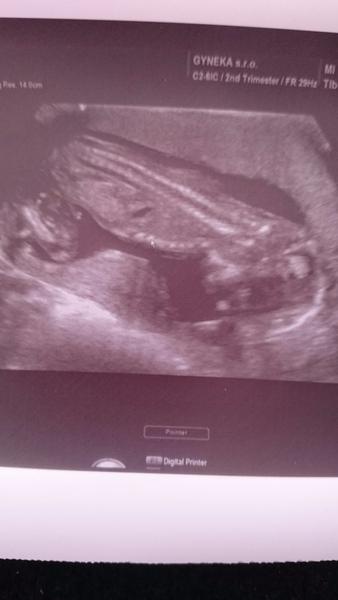

@alexslovakia tak toto je moj test na 11dpo. Dnes som 13dpo a zajtra rano mam krv...vyzera tak ze to do tretice klaplo.